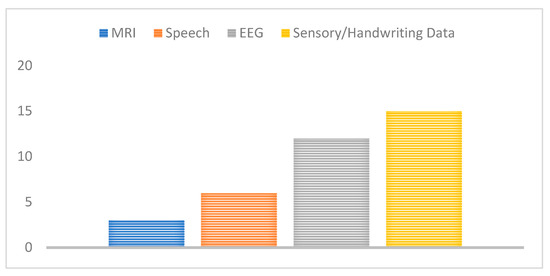

Further, datasets used for the detection and classification of PD have ranged from the EEG voltage signals to MRI scan images, handwriting images, and speech signals. We have therefore mapped the related work proposed to the used data type or modality in Figure 10, the majority of these studies have extensively used either EEG, or motion/sensory data to screen and diagnose PD. This may show a promising potential benefit for EEG and handwriting/sensory data to detect PD features and biomarkers, although they have not been clinically proven for disease diagnosis.

Figure 10.

Number of studies for each data type used.